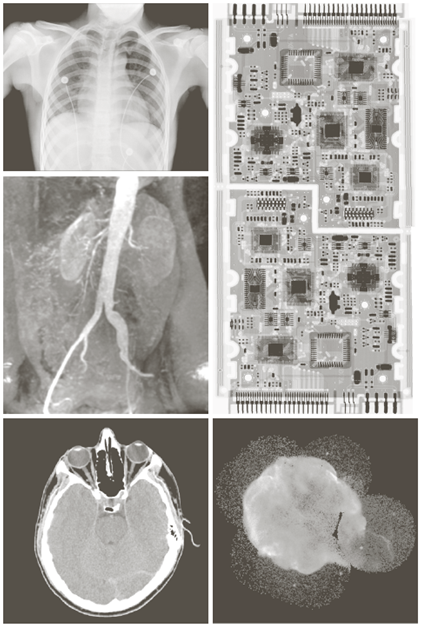

X-ray image

• X선의 투과성을 이용

Image

a) 항암제 Taxol b) 콜레스테롤 c) 마이크로프로세서